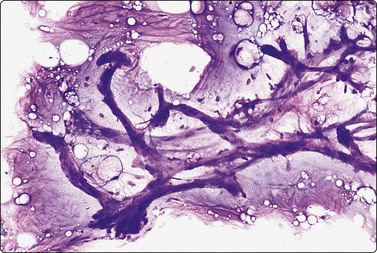

image image

Fig. 7.2 Non-neoplastic glandular breast tissue and low-grade duct carcinoma

Low-power view; (A) Bimodal population of epithelial sheets and single bipolar nuclei of non-neoplastic glandular breast tissue; (B) Single population of epithelial cells in low-grade carcinoma (MGG, LP).